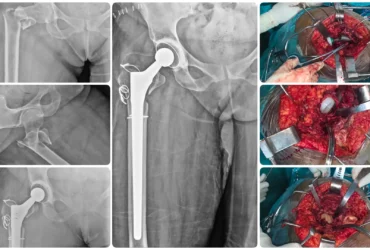

Complex Right Intertrochanteric Fracture Treated with Total Hip Arthroplasty | Balanku Hospital

Mrs. Parvathamma was treated at Balanku Hospital for a complex right intertrochanteric fracture using distal loading total hip...